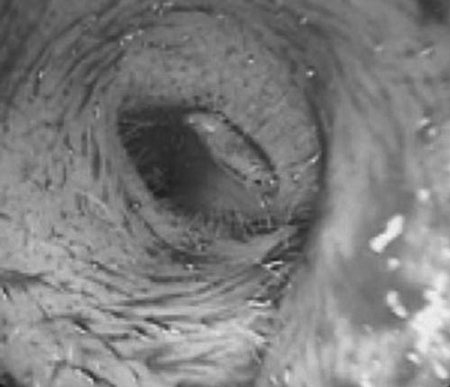

Old  Supseries Resize Lấy ổ ấu trùng ruồi trong tai một bệnh nhân

Ngày 10/12, tin từ Khoa Tai - Mũi - Họng (BV Trung ương Huế) cho biết các bác sĩ vừa thực hiện ca phẫu thuật lấy ấu trùng ruồi ra khỏi tai một bệnh nhân.

Vào ngày 8/12, bệnh nhân T.V.S. (trú xã Phong Bình, huyện Phong Điền, tỉnh Thừa Thiên – Huế) đã nhập viện ở BV Trung ương Huế với tai trái đau và nhức, có chảy dịch màu nâu hôi, riêng ống tai bị phù nề. Các bác sĩ của Khoa Tai - Mũi - Họng đã phát hiện trong tai trái của bệnh nhân S. có ấu trùng ruồi đang bò trong ống tai.

Trong tối cùng ngày 8/12, êkíp mổ gồm BS CK II Hồ Mạnh Hùng, Phó Trưởng khoa Tai - Mũi - Họng, BS CK II Đặng Như Quang (khoa Gây mê B) và BS nội trú Ngô Đức Lưu đã thực hiện ca mổ thành sau ống tai. Kết quả, ca mổ đã thành công, toàn bộ các ấu trùng ruồi đang sống được lấy hết ra khỏi tai bệnh nhân S.

Theo BS CK II Hồ Mạnh Hùng, Phó Trưởng khoa Tai – Mũi – Họng, đây là một trong những ca nhiễm trùng thuộc dạng nguy hiểm. Do ấu trùng các loại có thể tấn công từ tai vào não bộ một cách nhanh chóng cho nên nếu không phẫu thuật kịp thời, có thể ấu trùng sẽ ăn sâu vào não, dẫn đến nguy cơ tử vong cao.

Ấu trùng ruồi trong lỗ tai

Theo người nhà bệnh nhân, anh S. hiện đang qua Lào làm nghề thợ mộc ở Lào. Do tai nạn giao thông anh S. bị thương nhẹ ở vòng tai ngoài bên trái và được sơ cứu tại một cơ sở y tế. Những ngày sau, lỗ tai bệnh nhân tiếp tục đau nhức, chảy dịch nhiều. Anh S. nhập viện tiếp thì các BS đã lấy ra được 80 ấu trùng ruồi. Nhưng do vẫn đau nhức ở tai trái nên buộc phải chuyển vào BV Trung ương Huế.

Hiện bệnh nhân đang được điều trị bằng thuốc kháng sinh để ngăn chặn trứng ruồi nở, phát triển trong lỗ tai.